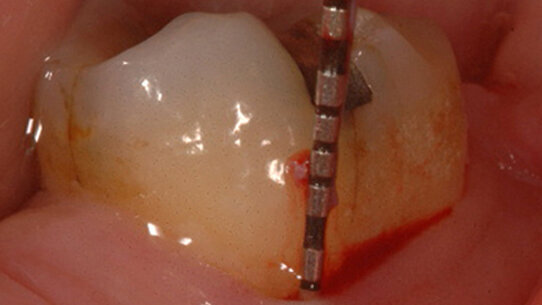

All’apertura della cavità d’accesso si osservava una parziale necrosi della polpa e un’incrinatura mesio-distale che si estendeva alle creste marginali ( Fig. 3).